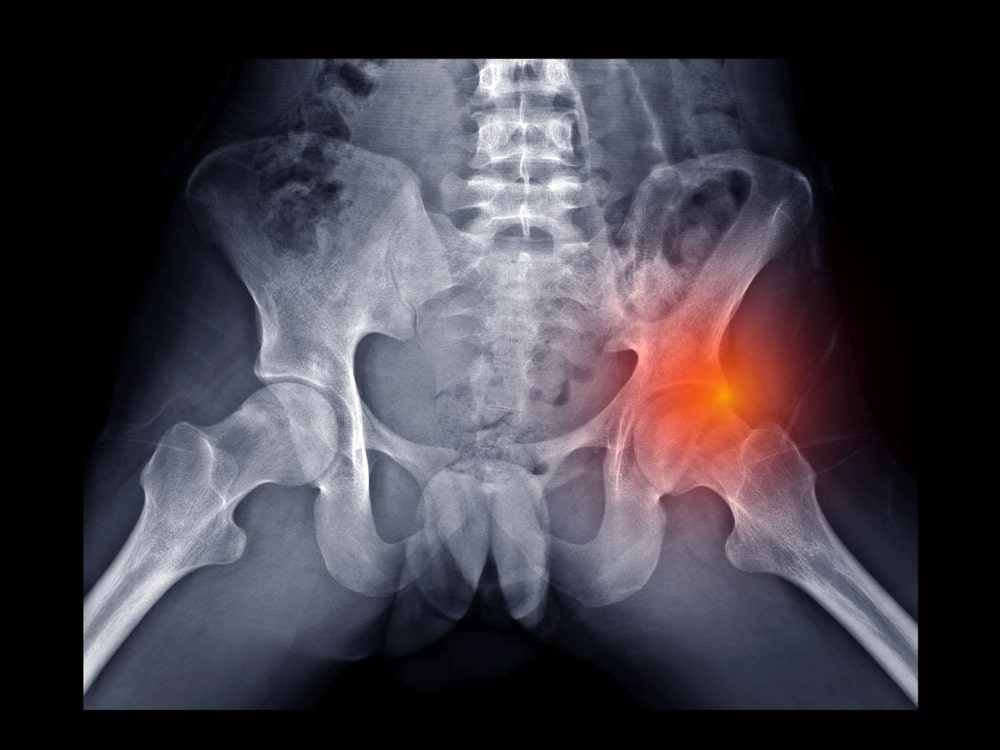

Think of your hip joint as a ball-and-socket. The ball is the head of your femur (thigh bone), and the socket is part of your pelvis (the acetabulum). Around the rim of that socket is a ring of cartilage called the labrum.

Femoroacetabular impingement (FAI) – where the ball and socket don’t quite fit together perfectly – can cause the bones to pinch the labrum. This can either be because the socket is misshaped or the femoral head, or both.